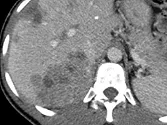

Figure 7. Carcinome hépatocellulaire traité par sorafénib.

Sur l’examen initial (A), la lésion présente deux compartiments sur cette image d’IRM au temps artériel l’un nécrotique, l’autre qui se rehausse, appelé tumeur « viable ».

B. Mesure selon mRECIST du plus grand diamètre de la lésion viable.

C et D. Après quatre mois de chimiothérapie, le compartiment viable de la tumeur passe de 37 à 24 mm, soit une diminution de 35 %. Il s’agit donc d’une réponse partielle, alors que le volume total de la lésion n’a pas changé.

Selon RECIST 1,1, la réponse aurait été « SD »